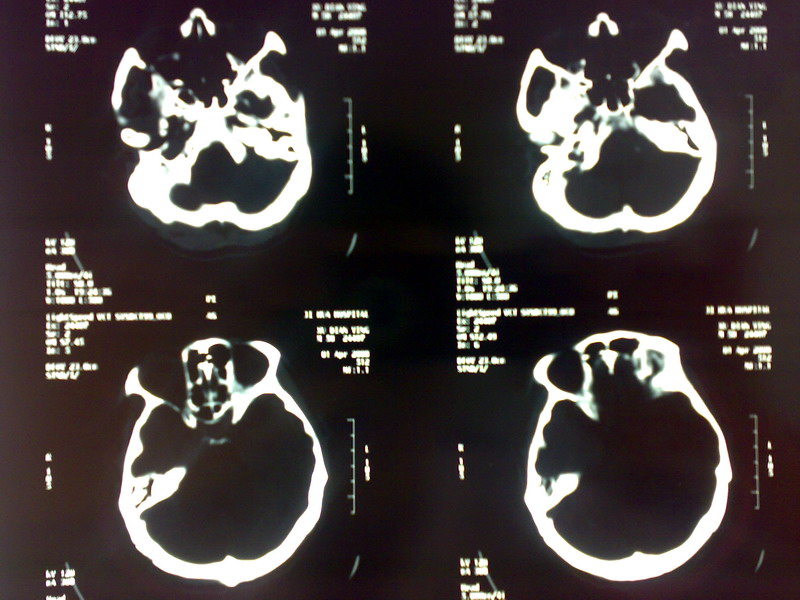

标题: CT12613:男 60 5个月前脑出血手术 现头外伤来诊 [打印本页]

标题: CT12613:男 60 5个月前脑出血手术 现头外伤来诊

脑出血术后改变,皮层下动脉硬化性脑病,腔梗,脑萎缩

考虑:1、左侧脑出血术后改变;

2、脑白质稀疏症。

1、脑出血术后改变 2、皮质下动脉硬化性病变 3、未见外伤性改变

2包括多发性脑梗塞、脑萎缩及脑白质病,再列出似有画蛇之嫌!

左侧脑出血术后改变,两侧基底节区多发脑软化灶及腔梗,脑白质变性,脑萎缩

左侧脑出血术后改变,两侧基底节区多发软化灶及腔梗,脑白质变性,脑萎缩

1、脑出血术后改变;  2、皮层下动脉硬化性脑病。